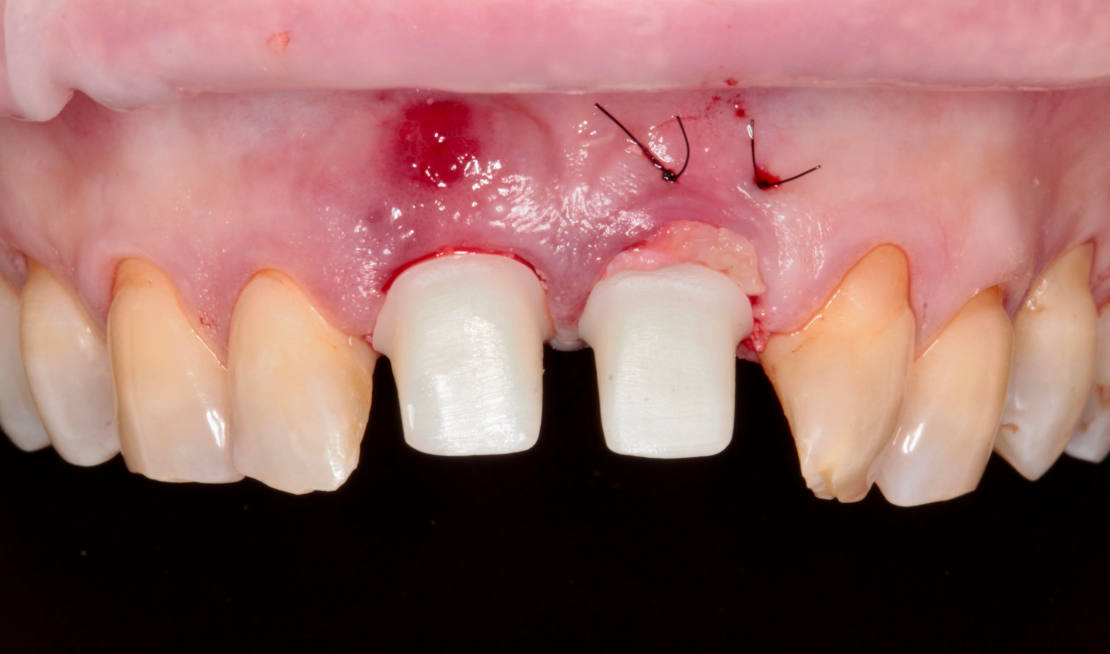

Vďaka týmto postupom bola operácia veľmi rýchla a pacientka odišla z ordinácie plne rehabilitovaná. Minimálne invazívnym spôsobom boli extrahované horné jednotky (obr. 6).

Následne sme použili protokol vŕtania a zavedenia implantátov cez šablónu (obr. 7, 8), na ktorej sme mali orientačné body pre správne napolohovanie implantátov, abutmentov a koruniek (obr. 9–14).

Posledné štúdie častejšie vedú k tomu, že z klinického hľadiska je stále preferovaný koncept jedného abutmentu, ktorý musí byť trvalý, nasadený hneď po implantácii a zostať v ústnej dutine až do nasadenia trvalej práce. Zachovanie prvotného prichytenia gingívy k protetickým komponentom má podstatný význam, najmä pri okamžitom zavedení implantátov po extrakcii zubov. Viacnásobné nasadenie a odstránenie protetických častí vedie k poškodeniu marginálnej časti gingívy, čo ovplyvňuje aj resorpciu kosti okolo implantátu. Ďalšou výhodou zirkónových supraštruktúr na implantátoch je aj to, že na povrchu zirkónu sa usádza menej bakteriálneho povlaku v porovnaní s titánovými, kovovými alebo keramickými materiálmi.